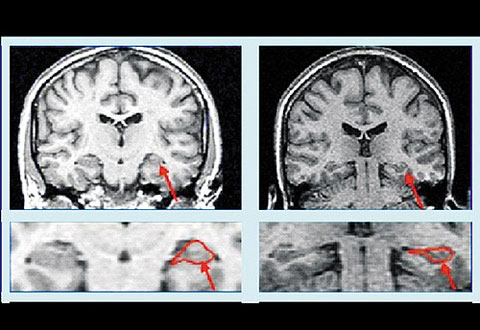

우울증이 생긴 뇌(사진 오른쪽)는 정상인의 뇌보다 해마(기억이나 공간 지각을 담당하는 부위)부위가 위축된다. / 서울아산병원 제공